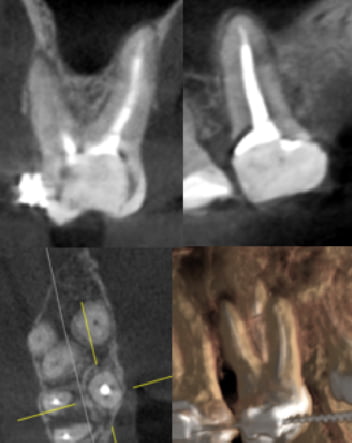

Описание эндодонтически леченого зуба

1.6 зуб

Коронковая часть: покрыта реставрацией, полость зуба заполнена состояние после эндодонтического вмешательства. Фиксирован брекет.

В палатинальном корне с округлым сечением визуализируется 1 корневой канал (1 тип по Vertucci

Перирадикулярные ткани: очаг радиолюценции в области фуркации корней, диаметром 7,5 мм, с распространением до периапикальной области

Пародонтальный статус: Уровень альвеолярной костной ткани на 2–3 мм ниже

Данное описание не является диагнозом. Необходима консультация специалиста.